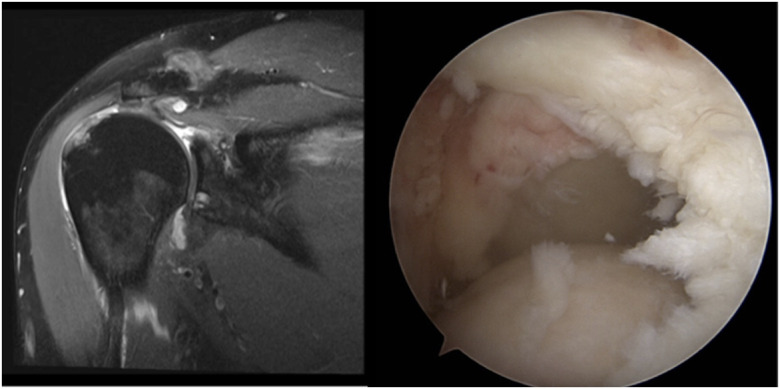

Augmentation Techniques for Rotator Cuff Repairs.

» Despite enhanced understanding of risk factors for failure and enhanced surgical repair techniques, the risk for failure of the rotator cuff to heal after surgery is still substantial.» A patient-specific approach to augmentation is essential, with decisions based on tear and patient characteristics.» Augmentation can improve repair strength and promote cellular infiltration, which collectively contribute to better healing outcomes.» Augmentation strategies may improve outcomes in rotator cuff repairs, particularly in high-risk cases; however, there is a lack of consensus among surgeons on the most effective strategies for each scenario.